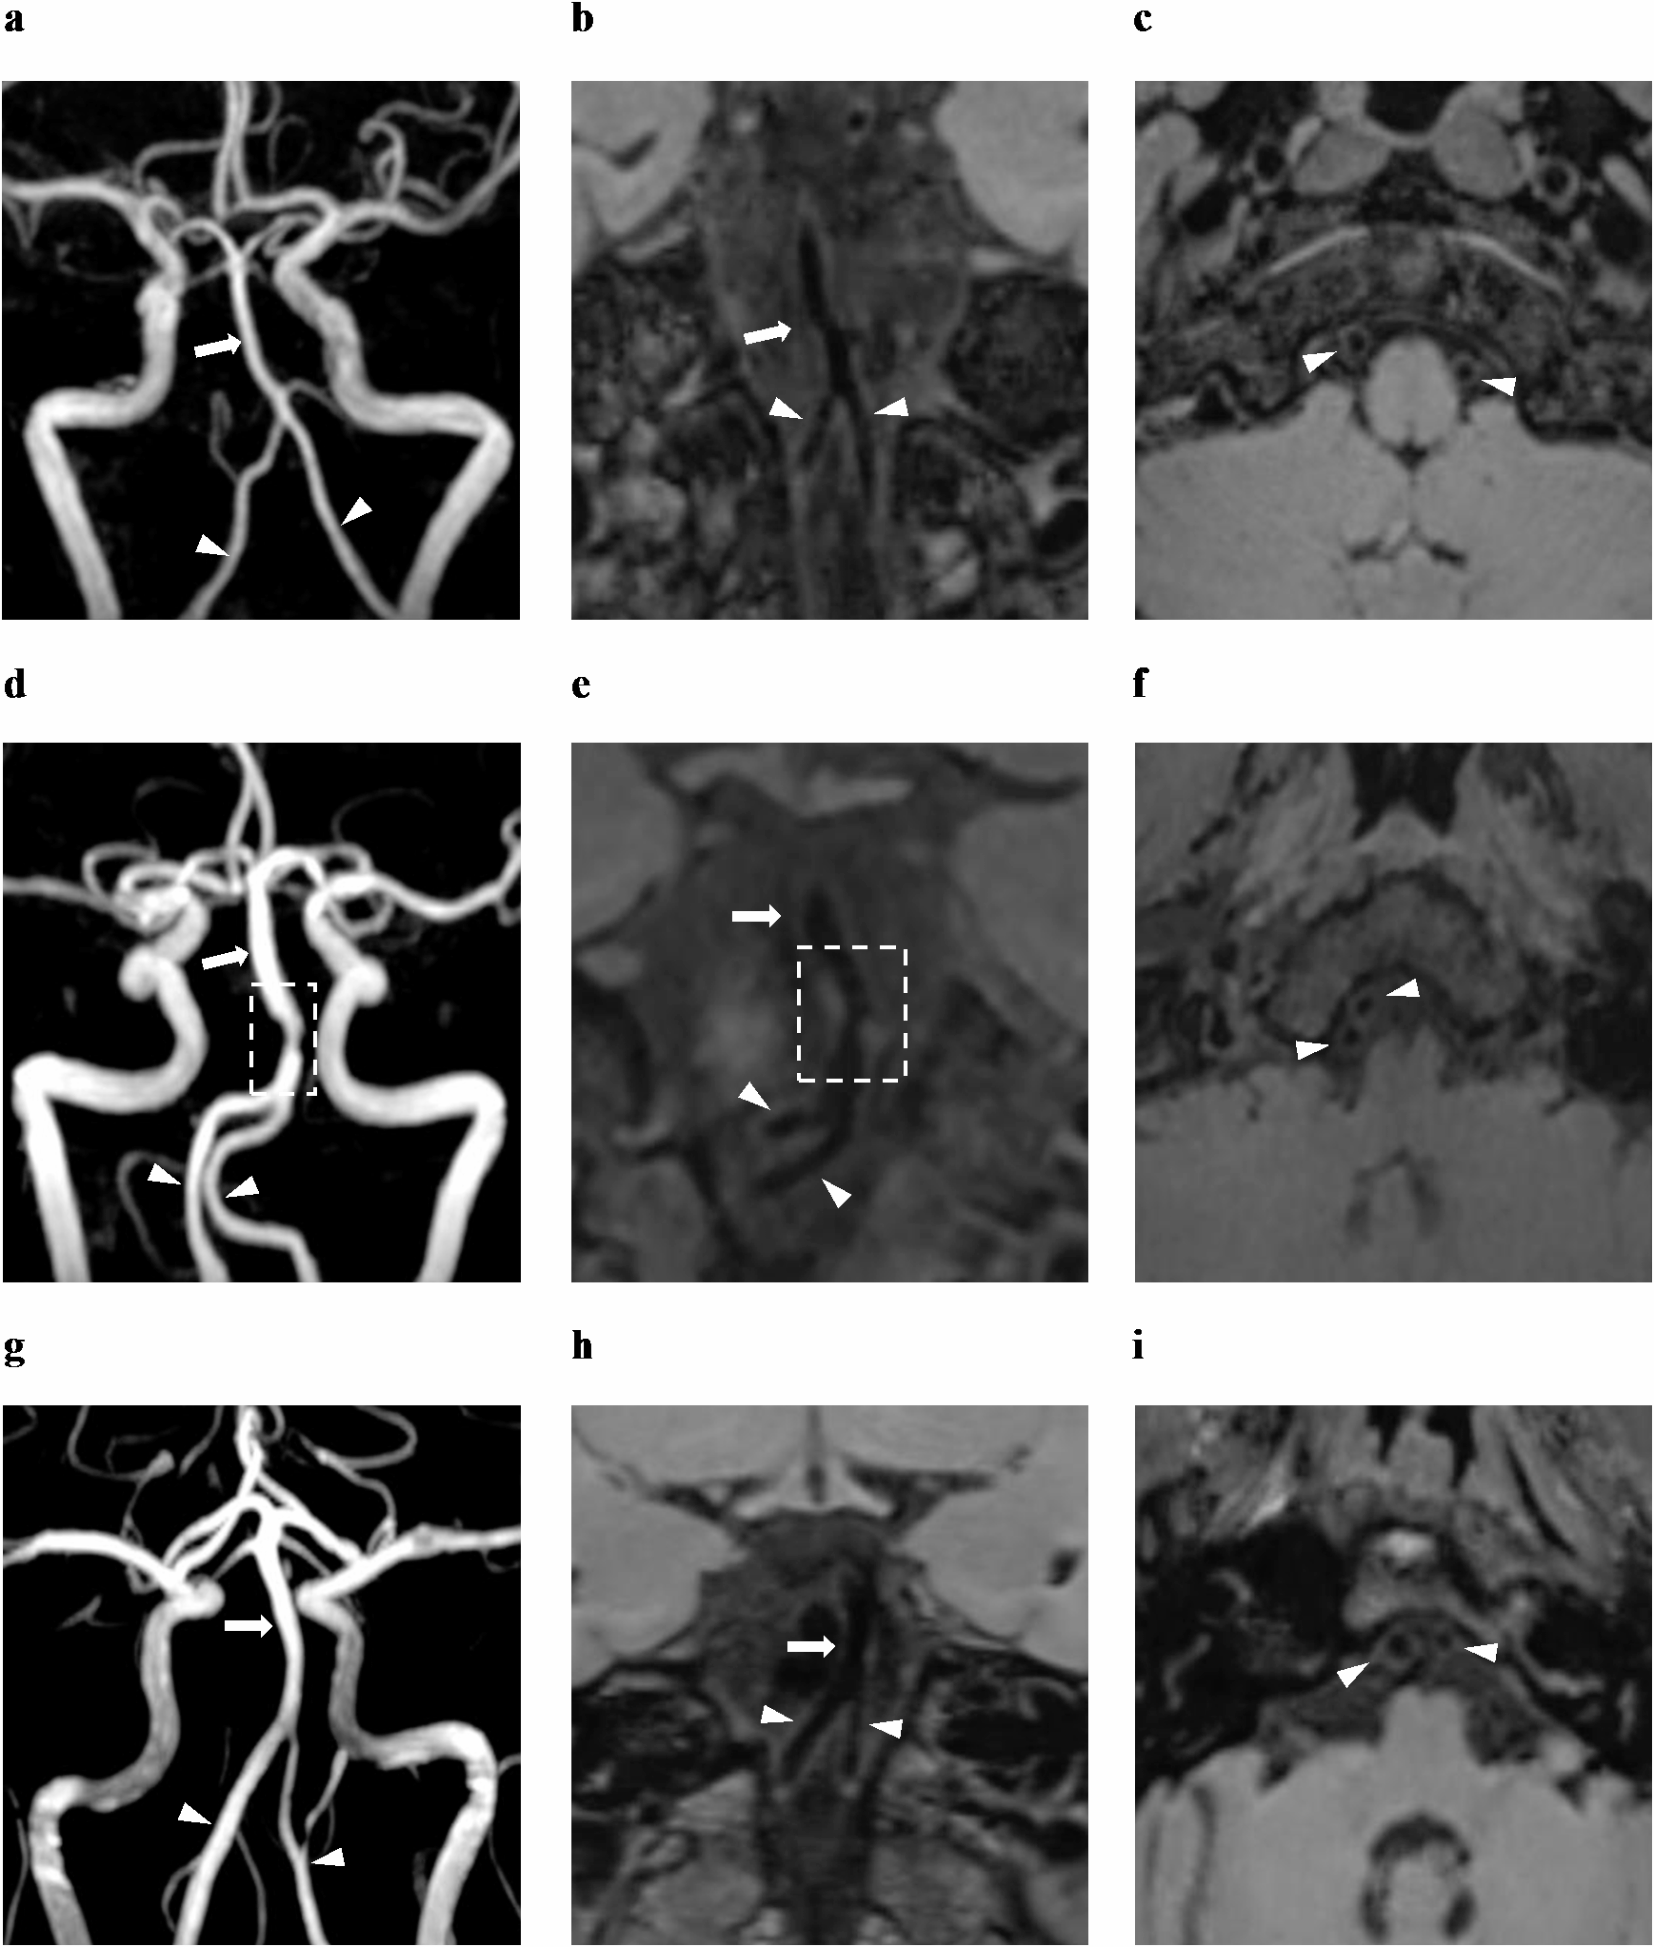

Fig. 2

3D TOF-MRA, coronal, and sagittal pre-enhanced T1W VWI images of tuning fork (a–c), walking (d–f), and lambda (g–i) configurations of VBA, presented sequentially. Arrows indicate BAs, and arrow heads indicate left and right VAs. The rectangle labeled stenosis of BA lumina resulted from atherosclerotic plaque (d,e). 3D TOF-MRA 3-dimensional time-of-flight magnetic resonance angiography, T1W T1-weighted, VWI vessel wall imaging, VBA vertebrobasilar artery, BA basilar artery, VA vertebral artery.